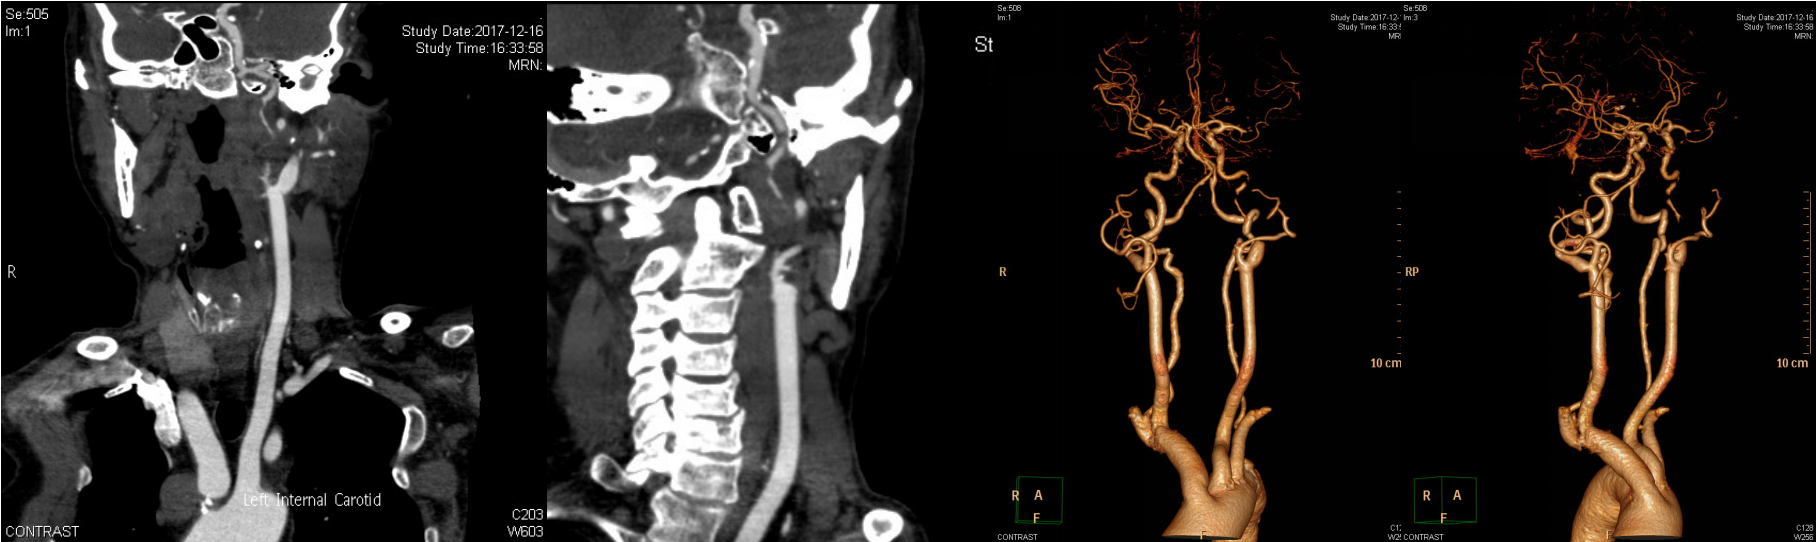

颈动脉CTA